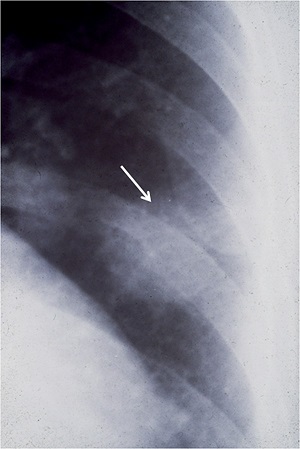

- Легочный дирофиляриоз у человека при поражении гельминтами легочной ткани человека. Дифилярии на первом этапе никак не проявляют себя, симптомы отсутствуют. Лишь при случайном проведении обследования (флюорография) снимок может и указать на наличие затемненных пятен с округлыми краями в легких. В ряде случаев у человека появляется кашель с отхаркиванием частиц крови, болезненность в груди, повышение температуры.

В случае легочного дирофиляриоза человека, инфекционные личинки мигрируют через венозную систему и умирают в правом желудочке, закупоривают легочную артерию, а также приводят к появлению фиброзных узелков в легких. Кратчайшее задокументированное время между отрицательным рентгеном грудной клетки и появление легочного узелка составляет 5 месяцев.

Только диагностика, а именно рентген (снимок) позволит выявить узелки до 1-2 см в диаметре. Иногда врачи путают дирофиляриоз с развитием злокачественной опухоли, поэтому требуется проведение развернутых диагностических процедур.

Проявления легочного дирофиляриоза сопровождаются признаками со стороны дыхательной системы. Наблюдаются болезненные ощущения в грудине, непродуктивный кашель (чаще), иногда появляется мокрота с кровью, одышка, увеличение температуры тела до субфебрильных цифр, озноб, общее недомогание. На коже всегда присутствует уплотнение, через которое проник паразит в организм.

Легочный дирофиляриоз практически всегда вызывает озабоченность у врачей по поводу возможного злокачественного образования. Для исключения такого диагноза проводят торакотомию (вскрытие) с открытой биопсией или клиновидную резекции легкого.

- рентгенография органов грудной клетки;

Лечение дирофиляриоза у человека с легочной формой заболевания подразумевает процедуру торакотомия проникновение через разрез на грудной клетке. После удаляют воспаленный узел, содержащий червя. После операции пациент находится в стационаре под постоянным наблюдением врачей. Консервативное лечение включает в себя медикаменты противовоспалительного, антигистаминного и успокоительного действия.

Осложнения встречаются редко. Наиболее распространенными из них являются неспецифические респираторные симптомы или небольшой легочный инфаркт. О внутриглазных, подконъюнктивальных и ретро-орбитальных инфекциях также сообщалось. Описан один случай развития менингоэнцефалита с афазией (нарушением речи), вызванный D. repens.

Худшее, к чему приводит легочный дирофиляриоз это необходимость открытой биопсии или клиновидной резекции пораженного участка легкого под средством торактомии (вскрытие), чтобы исключить серьезные заболевания. Висцеральная форма может служить причиной внутренних кровоизлияний.